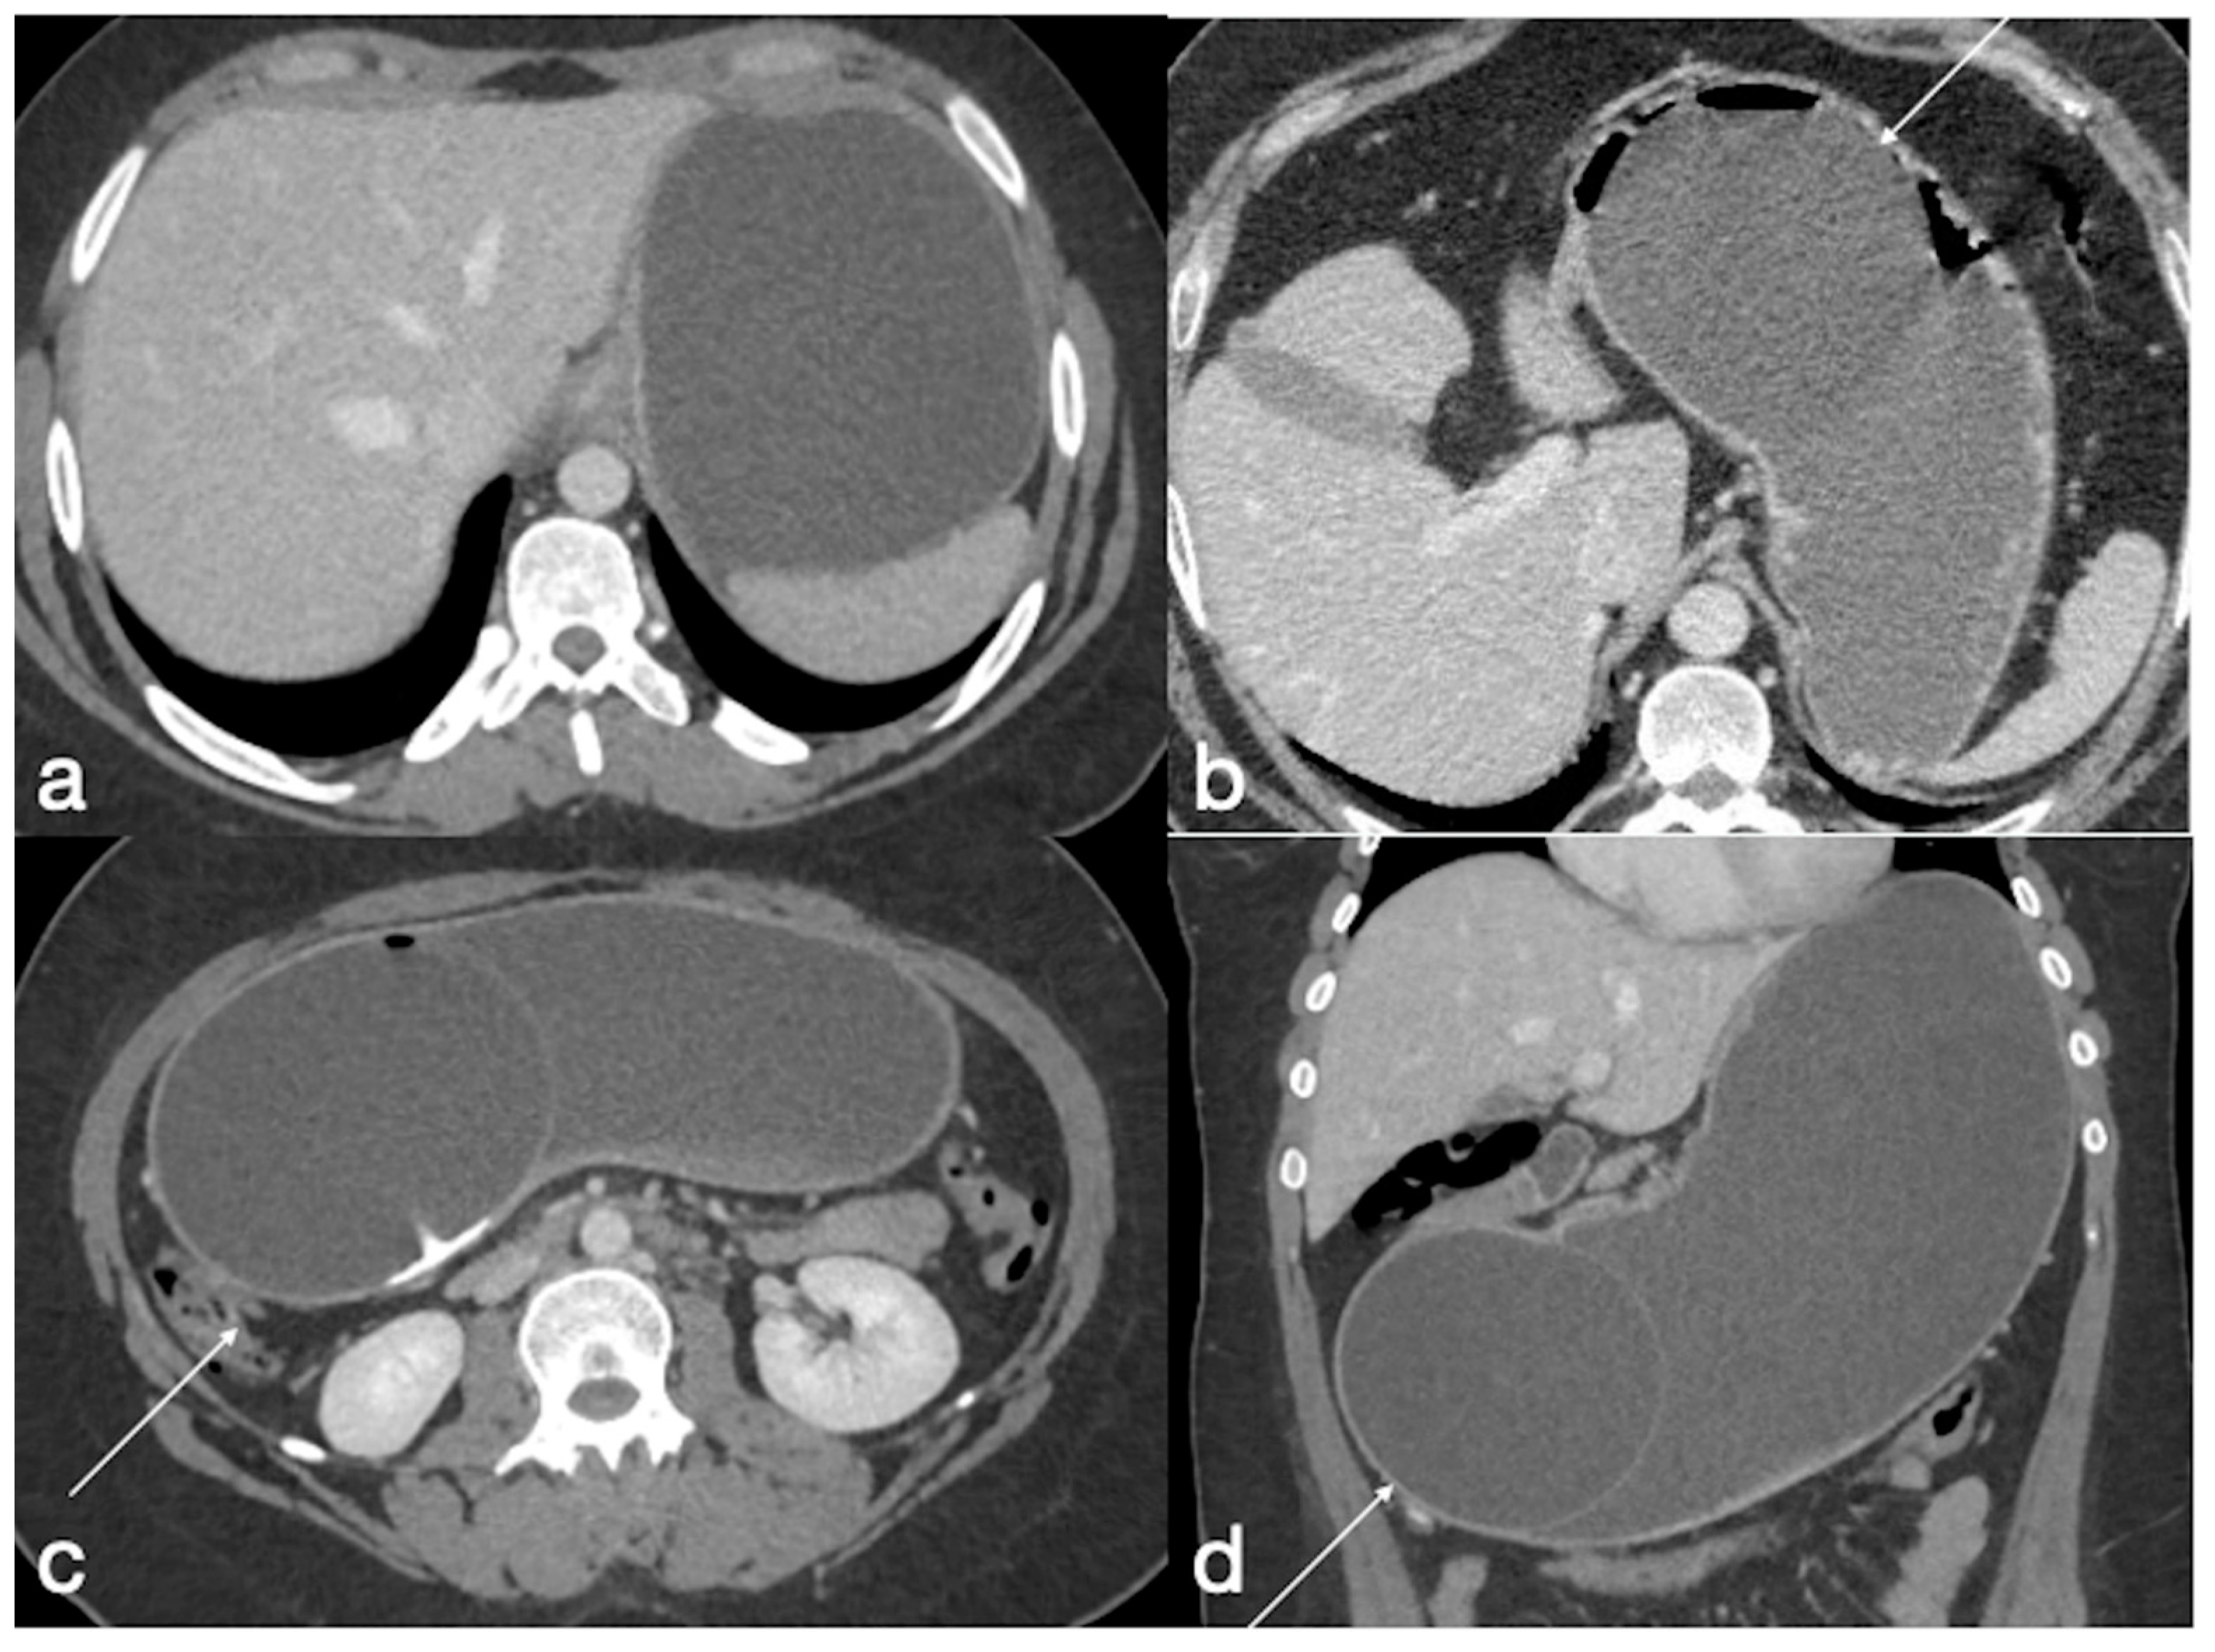

Figure 8. Gastric outlet obstruction. A 28-year-old female patient with a gastric balloon came to the emergency department complaining of sudden abdominal pain followed by persistent vomiting. Note the stomach overdistension proximal to the balloon, displaced in the antro-pyloric region (ac, axial views, d, coronal view; balloon, arrows).

Gastric outlet obstruction rarely occurs; indeed, it is reported that about 0.76% of balloons are complicated by gastric obstruction within the first two weeks of placement [10,23]. An early recognition and intervention is required, as gastric outlet obstruction secondary to an intragastric balloon may progress to necrosis and perforation.

Imaging findings:

UGI may show signs of gastric overdistension associated with impaired progression of endoluminal contrast medium.

The CT shows in detail the balloon within the gastric antrum associated with variable distension of the gastric lumen (Figure 8) [23].